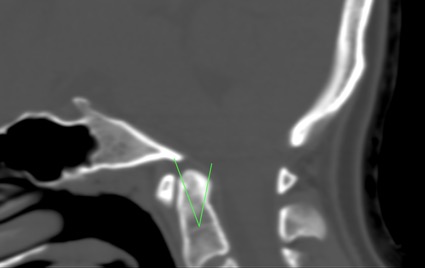

Ryc. 1 Wgłobienie podstawne. TK czaszki z linią Chamberlaina, która łączy tylną granicę otworu wielkiego z tylną granicą podniebienia twardego. Musi przejść przez wierzchołek wyrostka zębodołowego. W tym przypadku przekracza 5,3 mm.

Ryc 1.-Rozpoznanie przeprowadza się na podstawie pomiaru Fischgolda, linii bimastoidalnej Fischgolda i Metzgera, linii dwubrzuścowej Fischgolda i Metzgera lub bardziej znanych: linii MacGregora i Chamberlaina (ryc. 1).>